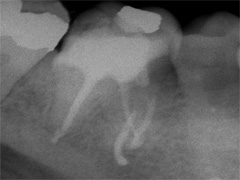

Als Zufallsbefund entdeckter, bis dahin beschwerdefreier apikaler Prozess an Zahn 36. Dessen insgesamt stark verengtes Innenraumsystem gestattete damals in erster Sitzung nur die Darstellung von 2 Kanälen. Wenn intensivstes Weitersuchen erfolglos bleibt, ist dem erfahrenen Behandler irgendwann zumindest so viel über den fehlenden Kanal bekannt: Er kann nicht sehr grosslumig sein und die Weitersuche auf den nächsten Termin zu verschieben ist nicht sehr riskant. Oft genug erlebt, gelingt dann frisch mindreseted und brainrebooted das in Sekunden, was zuvor in 20 min nicht gelingen mochte. So auch hier geschehen, bei der Suche nach dem 3. Kanal.

2 Aufnahmen sind von 2002 und die dritte vom 01.11.2010